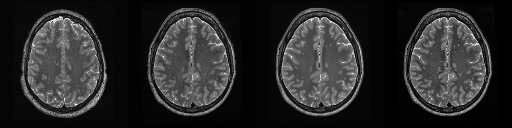

HCP T2w dataset

We utilize images from the publicly available Human Connectome Project (HCP) [51] T2-weighted (T2w) images dataset for the task of compressed sensing, which contains brain images from 47 patients. The HCP dataset includes cross-sectional images of the brain taken at different levels and angles.

Compressed sensing

We train a flow-based model from scratch on 10,000 randomly sampled images, utilizing the ncsnpp architecture [9] with minor adaptations for grayscale images. We employ compression rates , meaning . The measurement operator is given by a subsampled Fourier matrix, whose sign patterns are randomly selected. We evaluate our reconstruction algorithm’s performance on 200 randomly sampled test images.

We present the quantitative and qualitative results of compressed sensing in Tab. 1 and Fig. 4, respectively. As shown in Tab. 1, our method consistently achieves the best performance across varying compression rates . In Fig. 4, our method produces reconstructions that are more faithful to the original images, with fewer artifacts, leading to higher accuracy and clearer details.